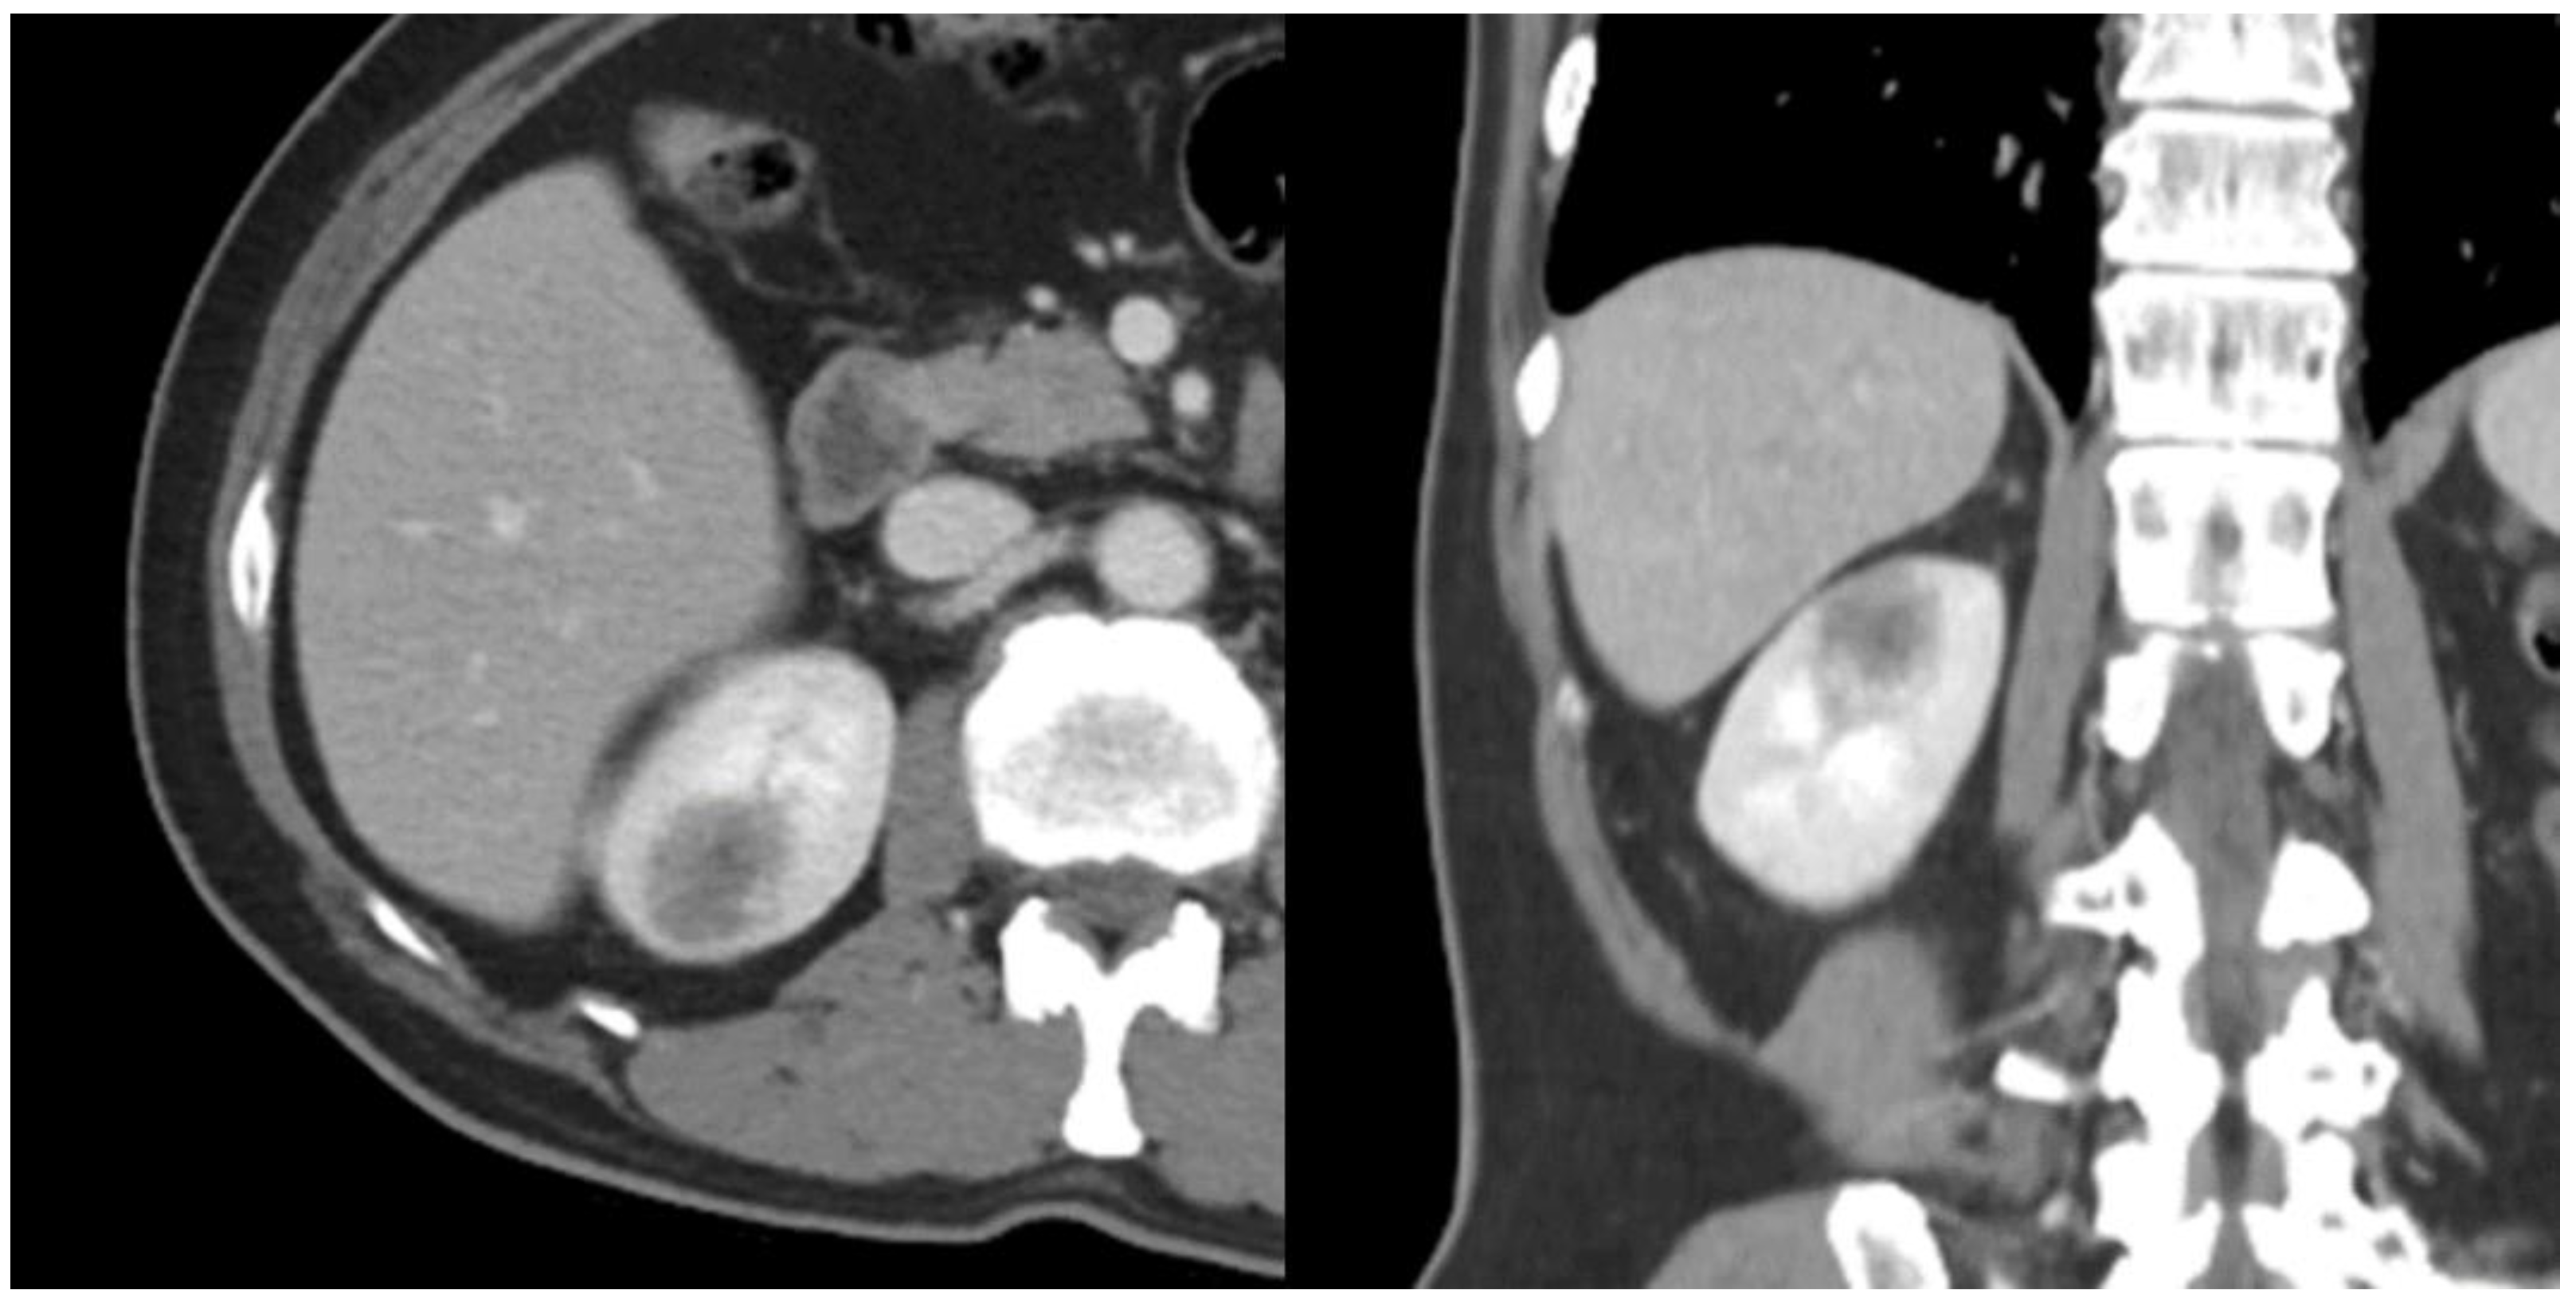

2. Case Report